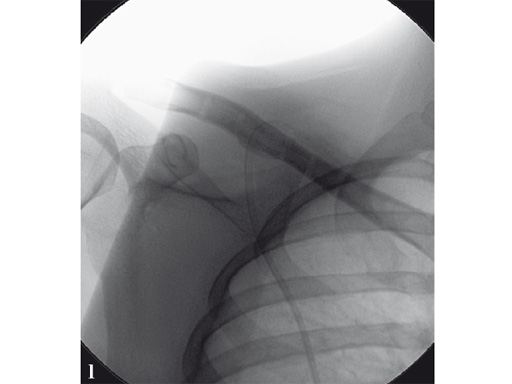

Case 1: a 30-year-old woman sustained a midshaft clavicle fracture. it healed with 2.1 cm shortening over 4 years after nonoperative treatment.

Case provided by Norbert Sdkamp and Martin Jaeger, Freiburg, Germany